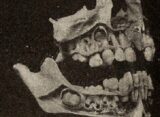

画像は「Mirror」より引用シェリダンさんが治療前に撮影した口の中の画像は衝撃的だ。前歯は白いどころか真っ黄色で、虫歯で黒ずみボロボロになってしまっている。奥歯にも健康な歯はまるで見当たらず、見ているだけで悪臭が漂ってきそうだ。